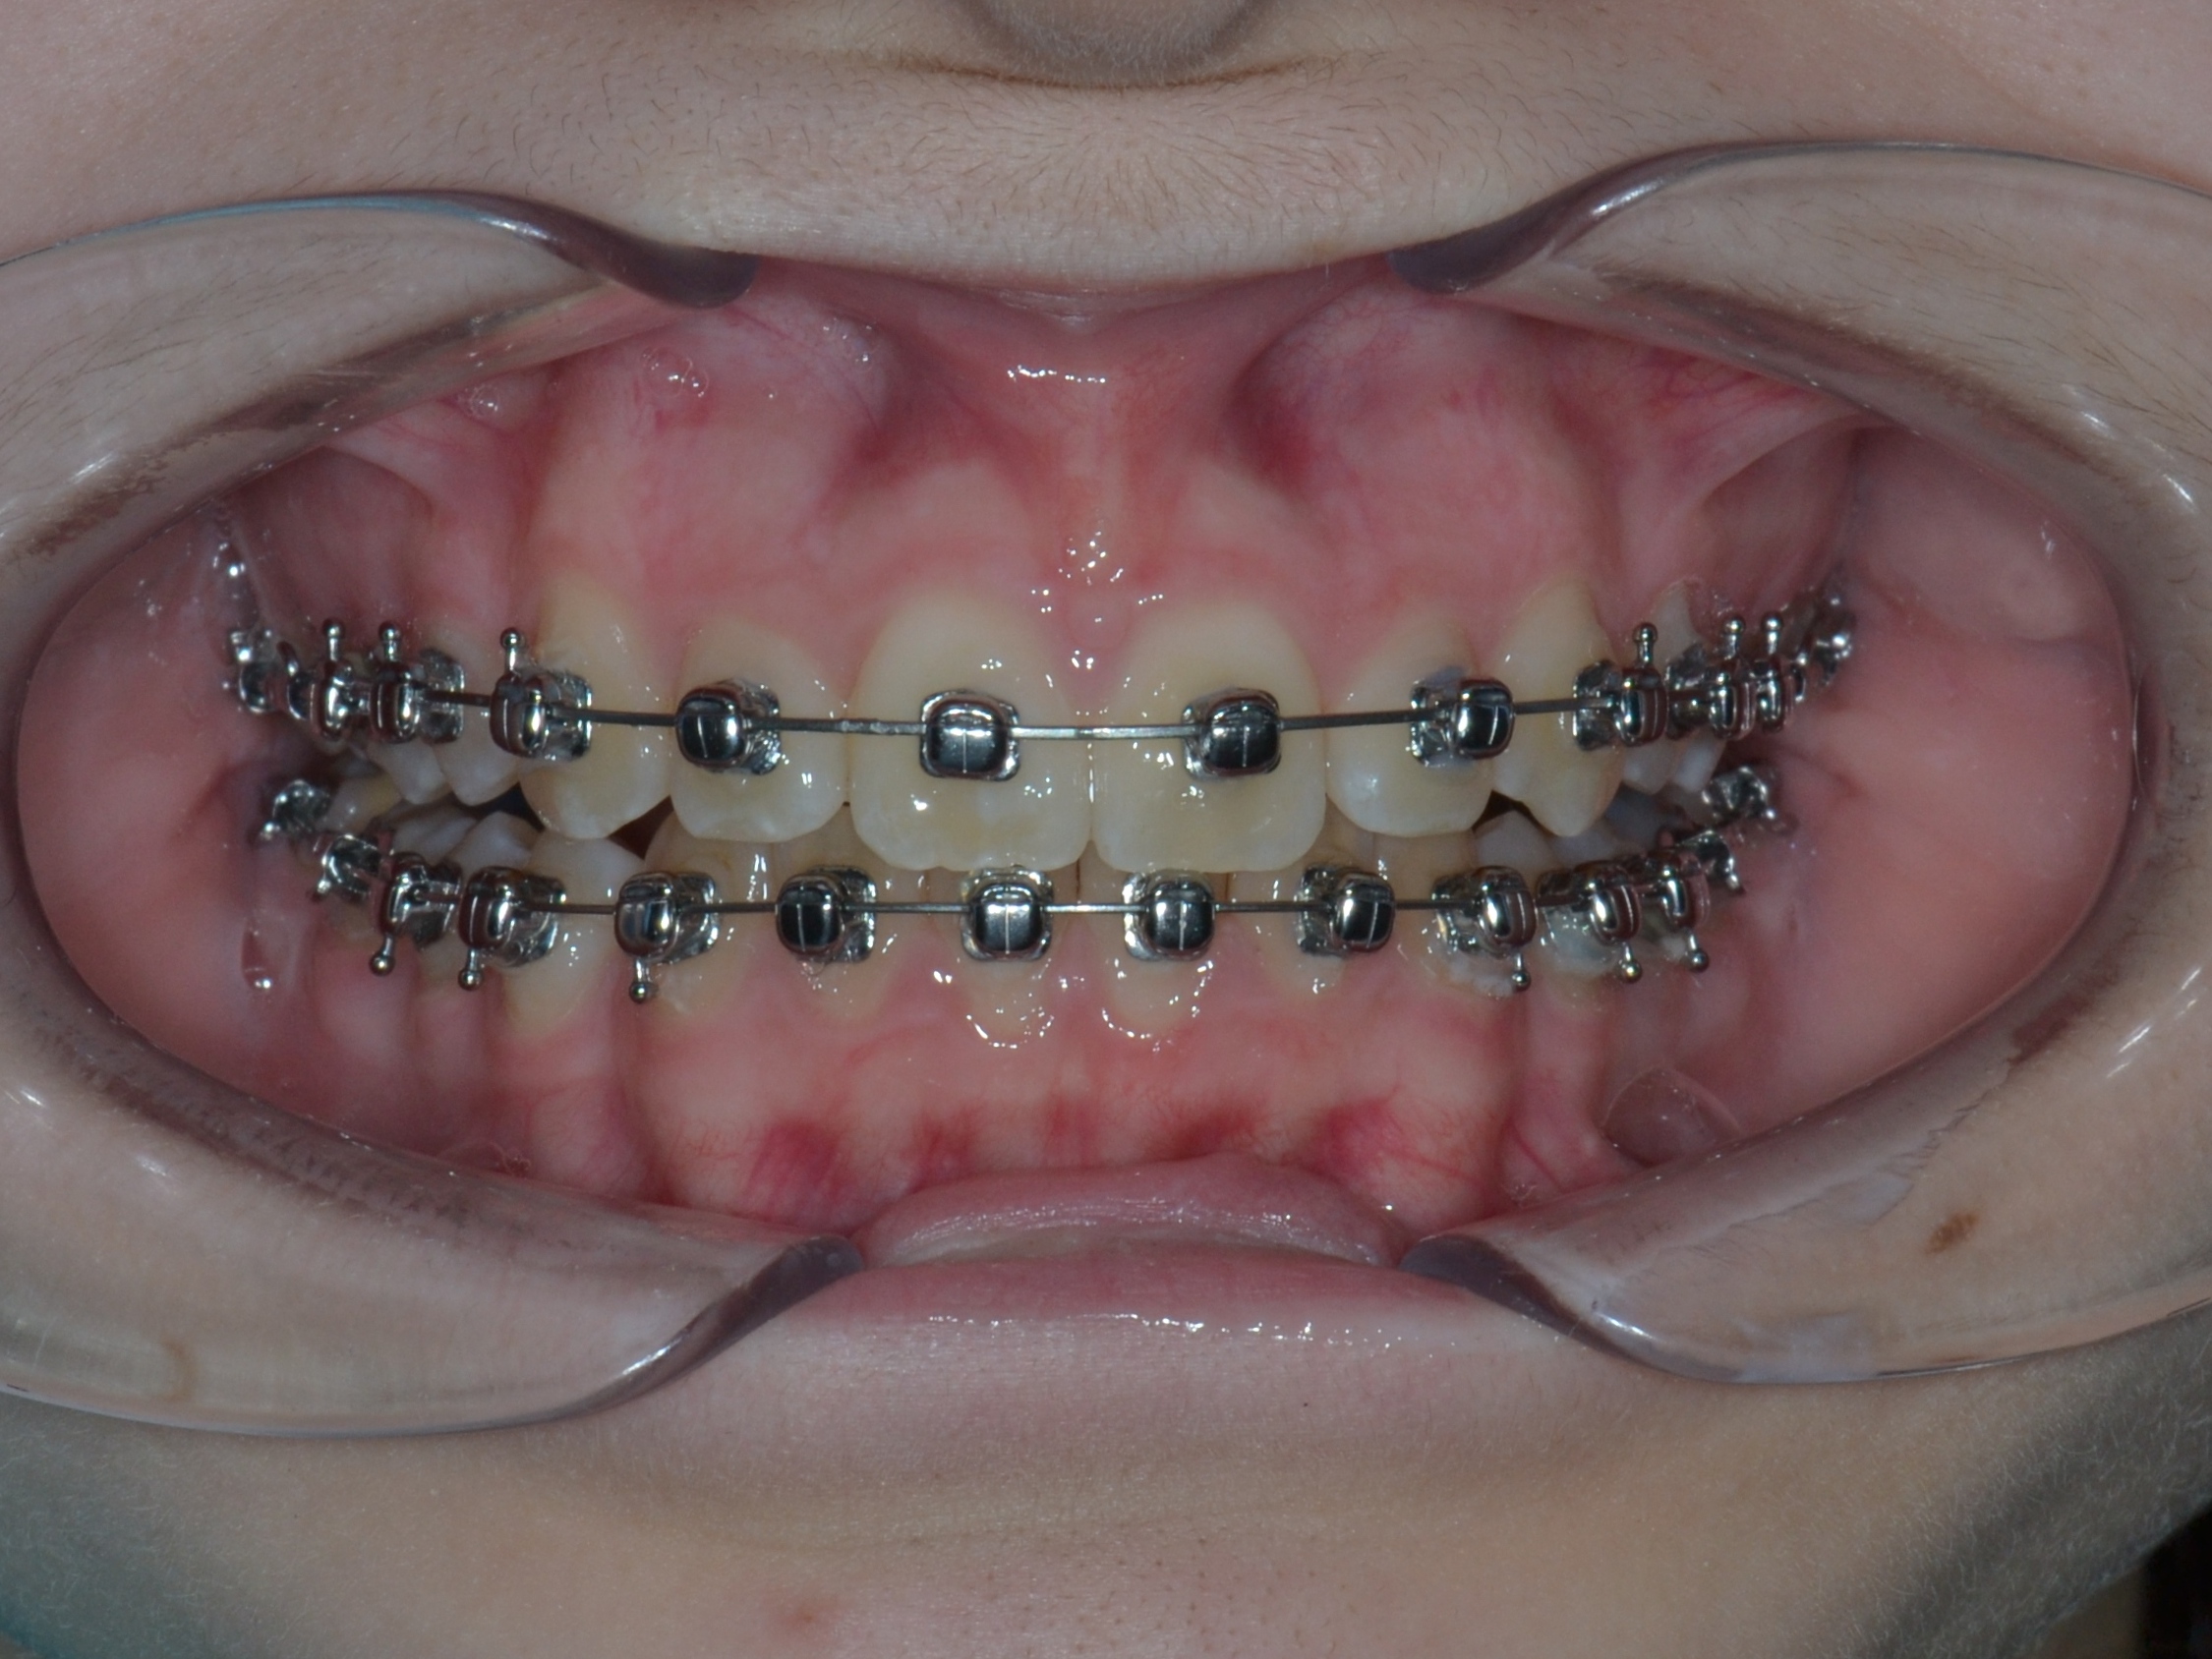

1

До фиксации

Июль 2024 г.